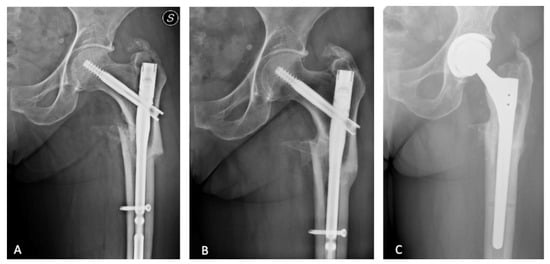

2.1. Surgical Procedure